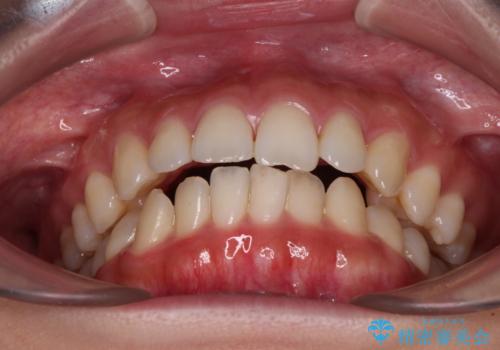

- 上下前歯の隙間と口元の出っ張った感じを気にして来院された患者様です。

上下の隙間は舌突出癖によるもので、またその癖により前歯が前方に出ている状態でした。

口元の出っ張りを改善するため、上下左右第一小臼歯4本を抜去し、ワイヤー装置にて矯正治療を行うこととしました。